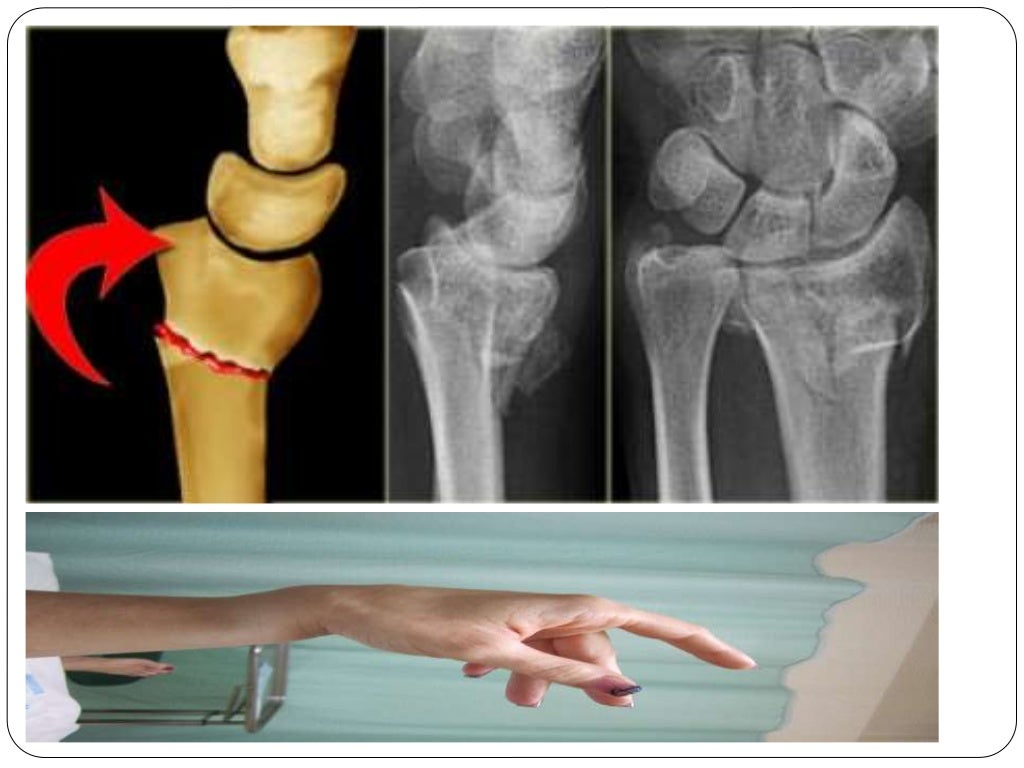

Fracture types Plaster Of Paris tecniques and Complications